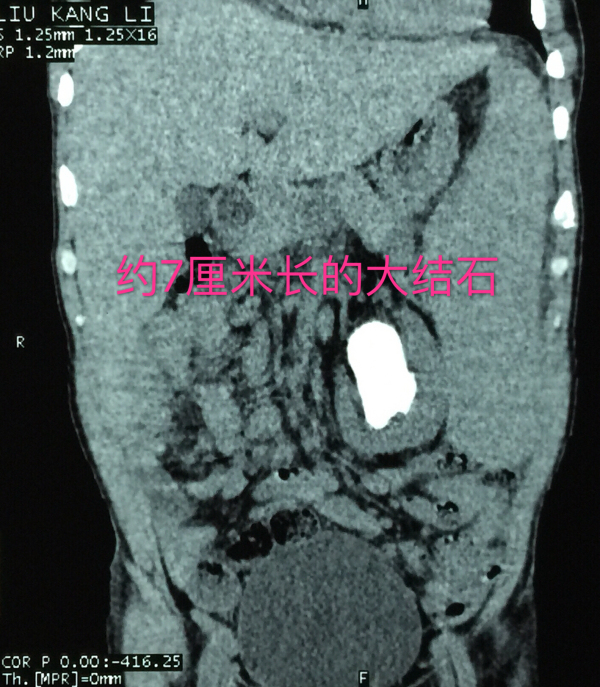

老刘白细胞149.59×10^9/L,右侧中上腹部有畸胎瘤占位,左肾结石非常巨大且复杂,而左肾又被白血病形成的巨大脾脏紧密包绕,还不包括胸膜和里三层外三层的肠道,从老刘的左肾取出结石无异于伸手从火红的熔铁炉内取出石头!要在老刘的身上做手术,将有80%的危险性,若不积极治疗,病人将面临100%的危险!

在老刘住院期间,泌尿外科的医生和护士众志成城,细心监护,一共请血液科、肿瘤科等科室专家进行了16次会诊,为他进行15次输血,2次抢救……虽然过程艰辛且曲折,但最终,泌尿外科的医护人员和老刘一起战胜了病魔,获得了成功,术后的老刘精神状态变得很好,白细胞值接近正常值,术后复查X光片显示结石被清理得很干净!12月10日,老刘顺利康复出院。出院当天,老刘一家还执意要和梁泰生主任合影留念以表感谢。

结石已被清理干净